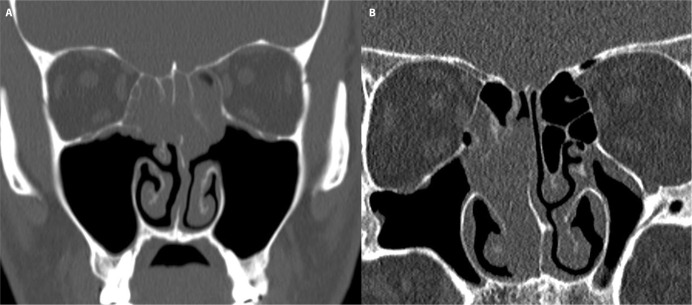

Results: Among 21 patients (17 males, 4 females; mean age 46.5 years), 11 cases (52.4%) exhibited bilateral origins (REAH_bi) in the superior nasal septum and olfactory cleft, while 10 cases (47.6%) presented as isolated unilateral lesions (REAH_uni). REAH_bi was significantly associated with asthma (p = 0.012), prior sinus surgery (p = 0.002), and inflammatory polyposis (p = 0.002) compared to REAH_uni. Elevated preoperative serum eosinophil levels and JESREC scores were also noted in REAH_bi cases (p = 0.021 and <0.001, respectively). Neither group showed recurrence during a mean follow-up of 11.91 months.

Conclusion: Bilaterally originating REAH in the superior nasal septum and olfactory cleft demonstrates pronounced type 2 inflammatory characteristics, suggesting potential differences in pathogenesis compared to unilateral REAH. These findings underscore the need for further investigation into REAH pathophysiology and emphasize the importance of bilaterality in clinical assessment.